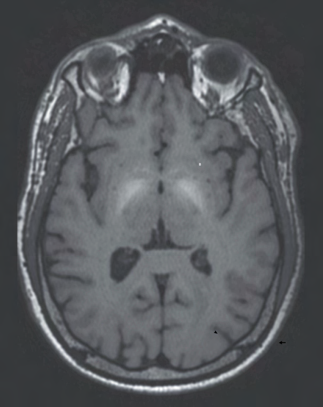

Recent studies indicate that Generative Pre-trained Transformer 4 with Vision (GPT-4V) outperforms human physicians in medical challenge tasks. However, these evaluations primarily focused on the accuracy of multi-choice questions alone. Our study extends the current scope by conducting a comprehensive analysis of GPT-4V's rationales of image comprehension, recall of medical knowledge, and step-by-step multimodal reasoning when solving New England Journal of Medicine (NEJM) Image Challenges - an imaging quiz designed to test the knowledge and diagnostic capabilities of medical professionals. Evaluation results confirmed that GPT-4V outperforms human physicians regarding multi-choice accuracy (88.0% vs. 77.0%, p=0.034). GPT-4V also performs well in cases where physicians incorrectly answer, with over 80% accuracy. However, we discovered that GPT-4V frequently presents flawed rationales in cases where it makes the correct final choices (27.3%), most prominent in image comprehension (21.6%). Regardless of GPT-4V's high accuracy in multi-choice questions, our findings emphasize the necessity for further in-depth evaluations of its rationales before integrating such models into clinical workflows.